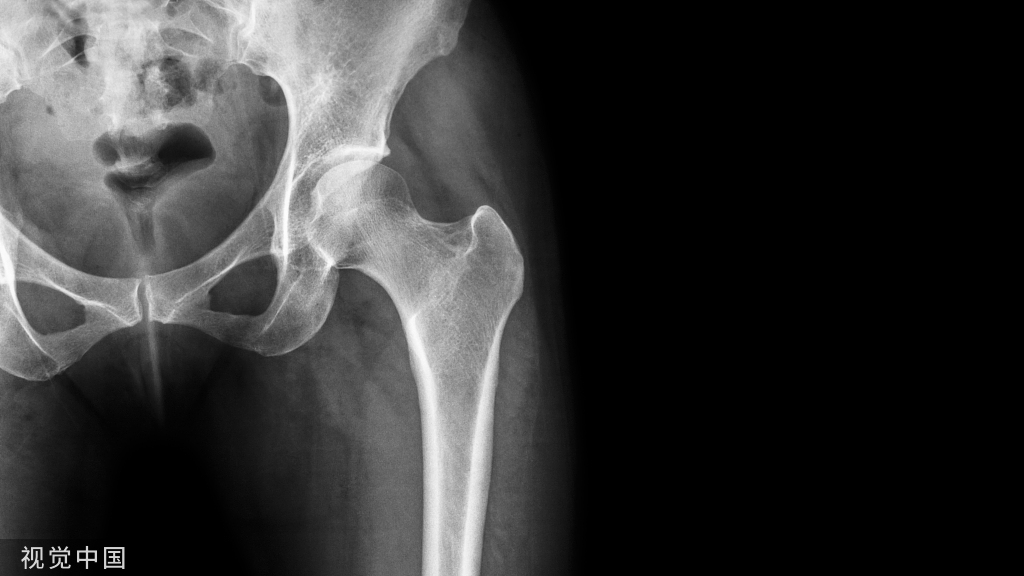

髋部骨折!